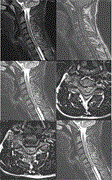

Diffuse large B-cell lymphoma mimicking the cervical epidural hematoma in a patient who underwent spinal manipulation therapy: a case report and literature review

Klaudia Kokot and others

Journal of Surgical Case Reports, Volume 2025, Issue 1, January 2025, rjae807, https://doi.org/10.1093/jscr/rjae807

Acute thoracic disc herniation with severe spinal cord compression: a case report

Mario Cahueque and others

Journal of Surgical Case Reports, Volume 2025, Issue 1, January 2025, rjaf001, https://doi.org/10.1093/jscr/rjaf001